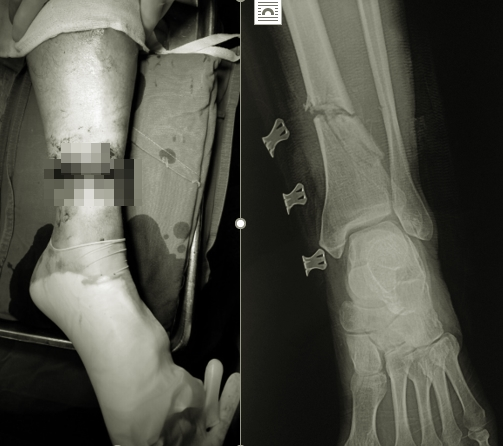

Bệnh viện Hữu nghị Việt Đức vừa tiếp nhận ông B.V.L. (56 tuổi, trú tại Hòa Bình) nhập viện trong tình trạng vết thương hở đứt 3/4 chu vi cẳng chân trái, chảy nhiều máu, mất vận động cổ chân. Các ngón chân, gãy hở xương chày, đứt hoàn toàn các gân cơ khu trước và sau cẳng chân, đứt bó mạch chày sau, chày trước.

Hình ảnh chấn thương của bệnh nhân.

Thông tin về ca bệnh, BS Hoàng Minh Thắng - Khoa Phẫu thuật Chi trên và Y học thể thao cho biết, ngay sau khi tiếp nhận, bệnh nhân được xử lý cố định ngoài xương chày, nối gân, thần kinh, nối động mạch chày trước, chày sau.